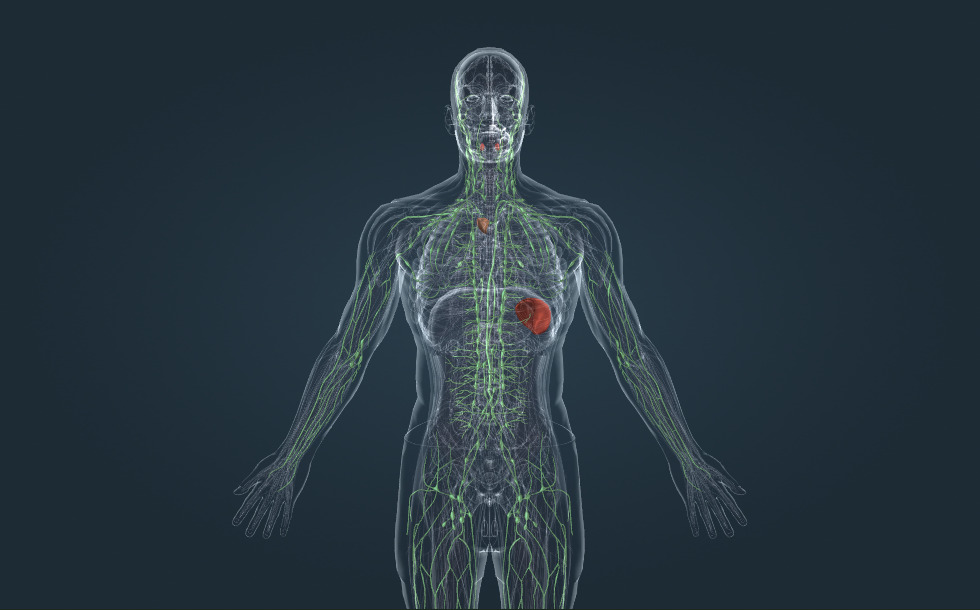

Hệ bạch huyết

- amiđan

- lách - Nó đóng vai trò quan trọng trong quá trình trưởng thành của các tế bào bạch cầu, do đó đóng vai trò quan trọng trong hoạt động của hệ miễn dịch.

- tuyến ức - Nó đóng vai trò quan trọng trong quá trình trưởng thành của các tế bào bạch cầu, do đó đóng vai trò quan trọng trong hoạt động của hệ miễn dịch.

- hạch bạch huyết - Nó đóng vai trò quan trọng trong quá trình trưởng thành của các tế bào bạch cầu, do đó đóng vai trò quan trọng trong hoạt động của hệ miễn dịch.

- ống ngực - Nó chảy vào tĩnh mạch dưới đòn trái, tại đây bạch huyết được trộn với máu rồi được vận chuyển xuống tim.

- mạch bạch huyết

Bạch huyết là chất lỏng có trong khoảng kẽ, còn được gọi là khoảng gian bào. Nó được sản xuất từ máu, bằng quá trình thẩm thấu qua thành mao mạch. Các sản phẩm chuyển hóa cũng được dẫn lưu trong bạch huyết. Bạch huyết được các mạch bạch huyết vận chuyển đi qua các hạch bạch huyết để tới tĩnh mạch dưới đòn. Các mầm bệnh được bạch huyết vận chuyển sẽ gặp các tế bào bạch cầu có trong các hạch bạch huyết, điều này rất quan trọng đối với chức năng của hệ miễn dịch. Các cơ quan bạch huyết quan trọng khác bao gồm tuyến ức, lách và amidan: các cơ quan này cũng đóng một vai trò quan trọng trong sự trưởng thành của các tế bào bạch cầu và trong chức năng bảo vệ của miễn dịch.

Bạch huyết là chất lỏng có trong khoảng kẽ, còn được gọi là khoảng gian bào. Nó được sản xuất từ máu, bằng quá trình thẩm thấu qua thành mao mạch. Các sản phẩm chuyển hóa cũng được dẫn lưu trong bạch huyết. Bạch huyết được các mạch bạch huyết vận chuyển đi qua các hạch bạch huyết để tới tĩnh mạch dưới đòn. Các mầm bệnh được bạch huyết vận chuyển sẽ gặp các tế bào bạch cầu có trong các hạch bạch huyết, điều này rất quan trọng đối với chức năng của hệ miễn dịch. Các cơ quan bạch huyết quan trọng khác bao gồm tuyến ức, lách và amidan: các cơ quan này cũng đóng một vai trò quan trọng trong sự trưởng thành của các tế bào bạch cầu và trong chức năng bảo vệ của miễn dịch.